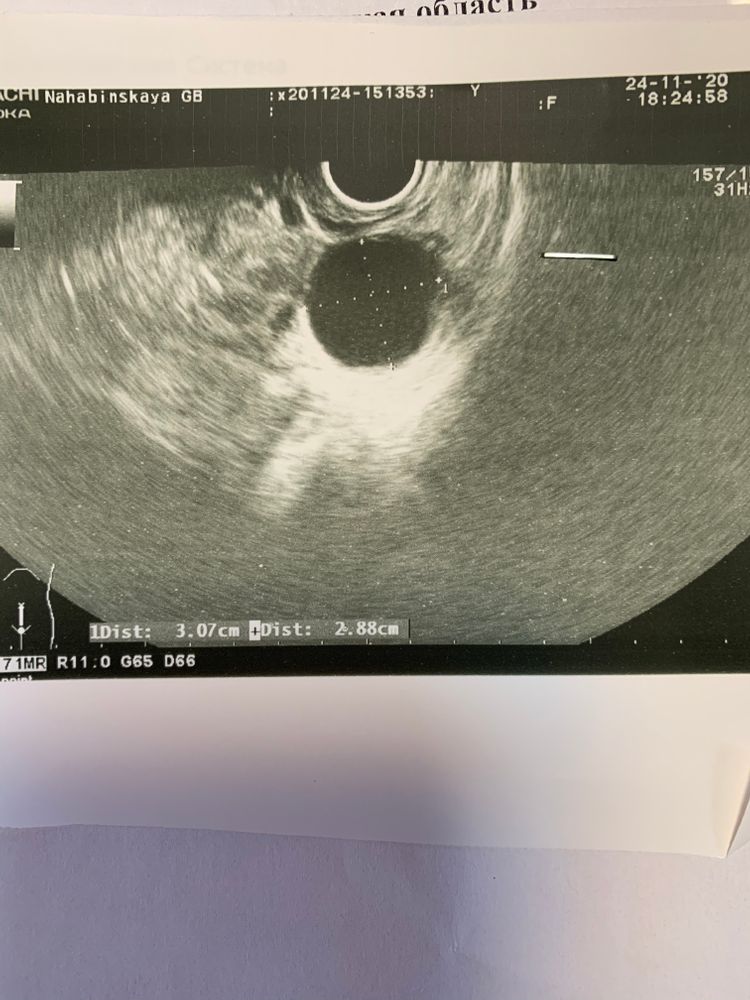

Для примера вот узи моих кист жт в других циклах и просто жт

По мне, так это киста ЖТ с кровотоком и жидкостью в ПМП, плюс эндик второй фазы.